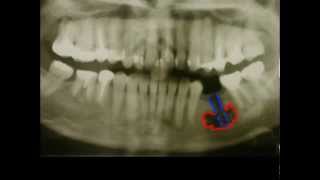

АНЕСТЕЗИЯ В СТОМАТОЛОГИИ (МАНДИБУЛЯРНАЯ, ТОРУСАЛЬНАЯ, ИНФИЛЬТРАЦИОННАЯ)